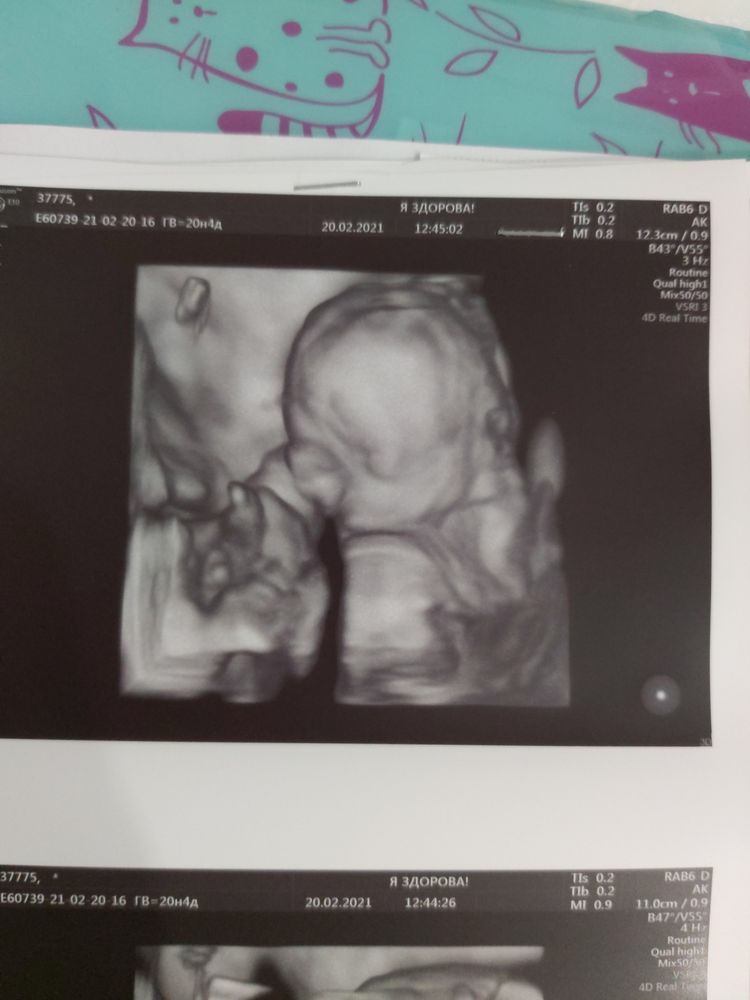

Немножечко фото нашей маленькой врединки🥰